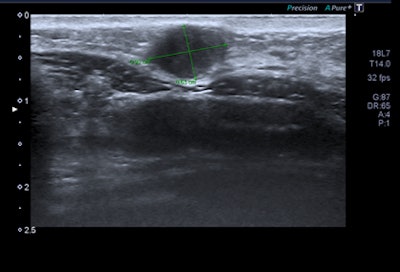

Loughran's impression was that longer and thinner breast masses were almost certainly benign, whereas the diagnosis was less certain with more rounded masses. This prompted him to conduct a retrospective study, recording the length and width of breast masses to determine whether the ratio could provide additional diagnostic guidance on the need for biopsy.

He reviewed 101 patients age 35 years or younger who had undergone ultrasound-guided breast core biopsy over a four-year period. The length and width of biopsied masses (recorded from images) and the ratio of length versus width of these masses were recorded. This information was easily evaluated using the calculator on a smartphone.

Loughran also correlated the ultrasound grade of suspicion (1 = normal, 2 = benign, 3 = probably benign, 4 = probably malignant, 5 = malignant) with the length-versus-width ratio. The data were later correlated with the histology.

Oval masses are well-recognized to more likely be benign, but Loughran asked, "How oval is oval?" An objective means of measuring the degree of "ovalness" may help more confidently determine those who require biopsy. An estimation of the degree of ovalness can be measured by establishing the ratio of length versus width in each mass, he told UKIO attendees.

"In general, the more rounded a mass, the more malignancy is likely. The more oval a lesion, the abnormality is more likely to be benign," Loughran stated. "However, other diagnostic criteria, including the nature of the lesional wall (smooth, poorly defined, lobulated, etc.) and the echo characteristics may further qualify the nature of the lesion."